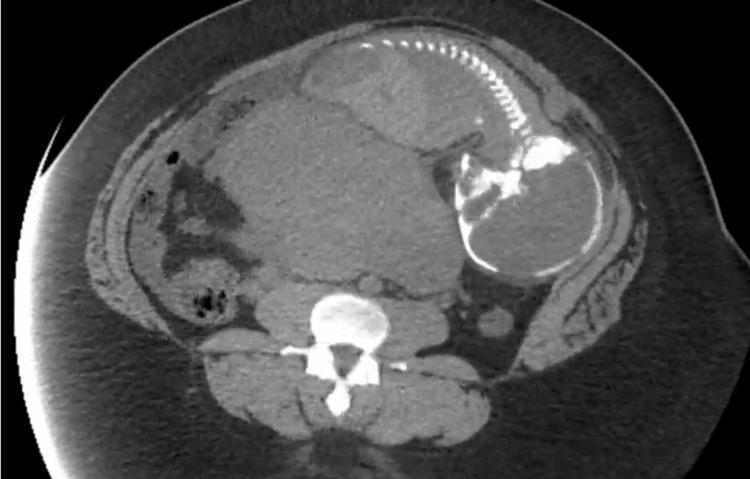

Ectopic pregnancy (EP) is a life-threatening condition requiring a high clinical suspicion. This diagnosis must be considered in all female patients of reproductive age presenting with abdominal pain or discomfort who may possibly be pregnant. Ectopic pregnancies occur in a small percentage of all pregnancies and are a significant cause of maternal morbidity and mortality. Abdominal ectopic pregnancy (AEP) is a rare and potentially fatal form of ectopic pregnancy where the implantation occurs in the abdominal cavity. We present the following case of a 23-year-old female who was transferred following an initial workup for abdominal pain and subsequently found to have an abdominal ectopic pregnancy at 37 weeks gestation. After transferring to our emergency department, the patient continued to have abdominal pain and her presenting FAST exam was positive for free fluid concerning for active hemorrhage and hematoma. Her clinical presentation was consistent with ruptured abdominal ectopic pregnancy, and she was taken to the operating room for emergent exploratory laparotomy and delivery. Her clinical course was complicated by adherent placenta and re-bleeding with significant hemoperitoneum requiring re-entry laparotomy and transfusion. We present the details of this case along with the diagnostic imaging and management of the rarely seen and life-threatening condition of secondary abdominal ectopic pregnancy (AEP).

异位妊娠(EP)是一种危及生命的情况,需要高度的临床怀疑。对于所有出现腹痛或不适且可能怀孕的育龄女性患者,都必须考虑这一诊断。异位妊娠在所有妊娠中占比很小,是孕产妇发病和死亡的重要原因。腹腔异位妊娠(AEP)是一种罕见且可能致命的异位妊娠形式,其着床发生在腹腔内。我们呈现以下病例:一名23岁女性,因最初的腹痛检查后被转诊,随后在妊娠37周时被发现患有腹腔异位妊娠。转入我们的急诊科后,患者持续腹痛,其床旁超声检查发现有游离液体,提示存在活动性出血和血肿。她的临床表现与腹腔异位妊娠破裂相符,于是被送往手术室进行紧急剖腹探查和分娩。她的临床过程因胎盘粘连和再次出血伴大量腹腔积血而复杂化,需要再次剖腹手术和输血。我们展示了该病例的详细情况以及继发性腹腔异位妊娠(AEP)这种罕见且危及生命状况的诊断影像学和处理方法。